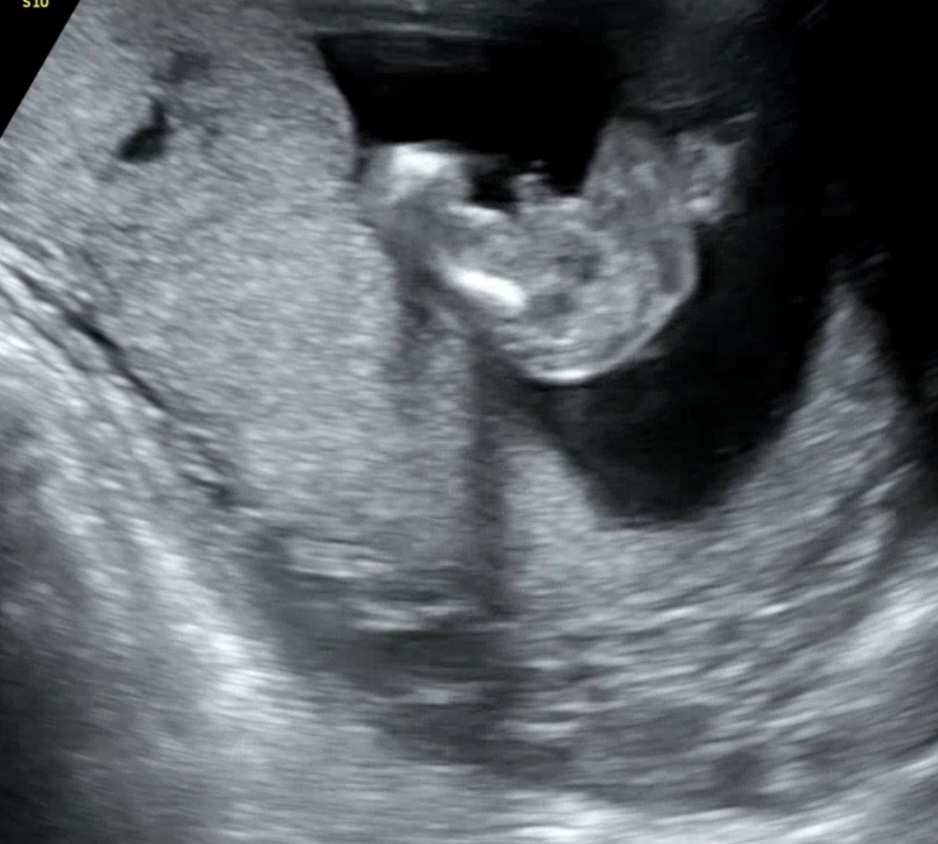

딸이 될순없겠죠? 15주5일

딸을 너무바래서 이름도 미리생각했는데.. 21주에 반전은없겠죠?ㅋㅋㅋㅋ

오동통 너무 귀엽습니당🥰아들에 한표요ㅋ

엉덩이가통통 귀엽네요 ㅋㅋ 아들같아요

네...고수는아니지만..아들인거같아요~